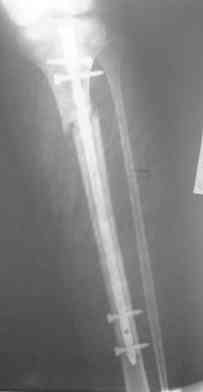

Интрамедуллярный остеосинтез. Как избежать смещение? |

Была прооперирована девушка 17 лет и получена такая Ro-картина.

На сколько критично подобное смещение,

каких последствий можно ожидать и как его упреждать а дальнейшем?

В клинике отсутствует ЭОП!